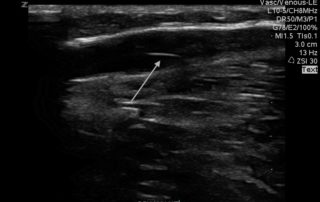

Vein Care Delivered To Your Home: In-home ultrasound diagnostics

We now offer mobile ultrasound services!

Enjoy a thorough vascular assessment from the convenience of your own home.

- For the ultrasound portion, our Registered Vascular […]